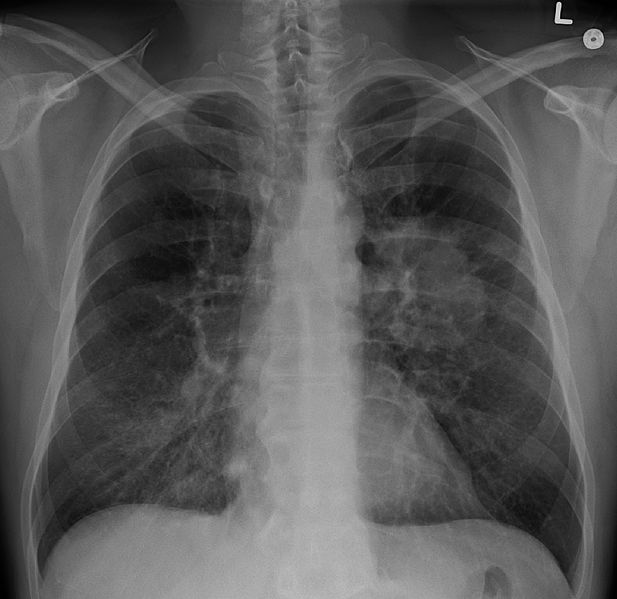

Au démarrage du projet en août 2013, le crizotinib est une thérapie ciblée d’administration orale autorisée seulement pour le traitement des patients qui souffrent d’un cancer du poumon non à petites cellules (CPNPC) présentant une altération moléculaire spécifique (translocation de ALK) dans leur tumeur. Ce cancer est le plus fréquent des cancers du poumon : il représente environ 85 % des cas (source : Cancer bronchique non à petites cellulles / Référentiel national de RCP, collection Référentiels et recommandation, INCa, 2015). Cependant, le crizotinib agit sur trois cibles moléculaires ALK, MET et ROS1 qui sont retrouvées dans plus d’une quinzaine d’autres cancers.

• Dans le cancer du poumon non à petites cellules, AcSé crizotinib a montré l’efficacité du médicament dans les tumeurs présentant une altération de ROS, ou encore une mutation ou une amplification de MET. Au vu des résultats intermédiaires, une recommandation temporaire d’utilisation a été accordée, au cours de l’essai, dans les CPNPC présentant une translocation de ROS1. Le crizotinib a ensuite été approuvé en Europe dans cette nouvelle indication du cancer du poumon en 2016. Les taux de réponse dans les CBNPC présentant une mutation de MET apportent des éléments en faveur d’une nouvelle extension d’indication.